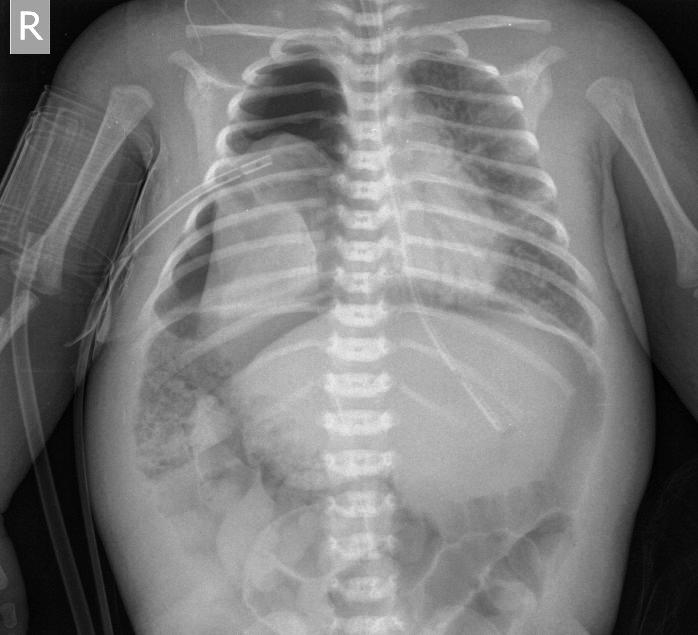

Поскольку картинка "до того как" активности не вызвала, добавлю картинку после того как в ситуацию вмешался хирург. Может быть станет яснее...

CR0002 (2).jpg

Была задренирована правая плевральная полость, в первую очередь воздух ушёл из живота.

После всех этих проблем ребёнок прожил ещё около 2-х недель. На секции - правосторонняя ложная диафрагмальная грыжа, гипоплазированное безвоздушное правое лёгкое.